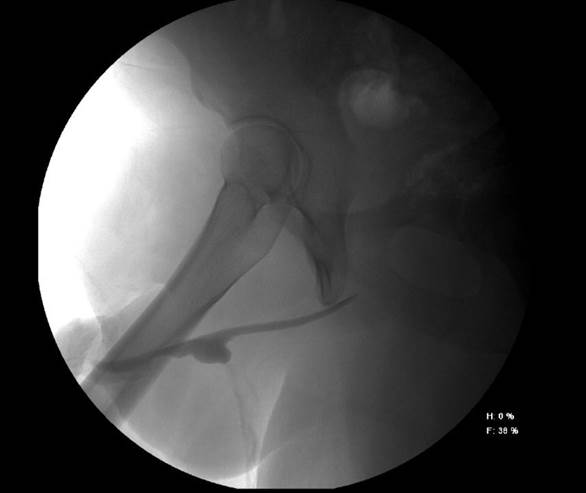

Paciente masculino de 21 años, con antecedente de hipospadias de uretra peneana distal, precedente de siete intervenciones quirúrgicas previas para corrección de hipospadias fallidas durante la niñez y adolescencia, acude a consulta por presentar micción a diferentes niveles de la uretra peneana distal (Figura 1), uretrocistografía del hipospadias (Figura 2) y solicita tratamiento para resolverlo.

Figura 2 Se observa fuga de medio de contraste a nivel central y permeabilidad de uretra distal y proximal a jeringa con medio de contraste